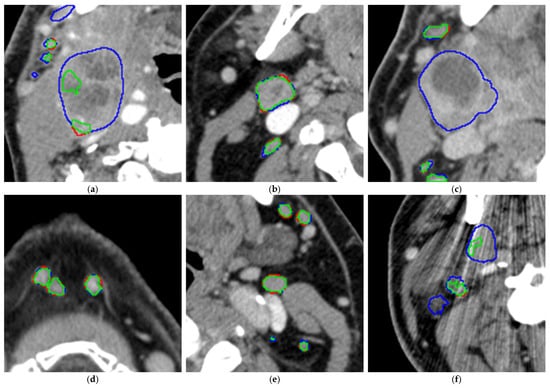

To obtain a better visual impression of the segmentation accuracy of both smaller and larger LNs, the radiologist looked at an overlay of the CT scan with both the manual segmentations and the segmentations performed by the AI model (see Figure 5).

The model tends to leave out the necrotic parts of the metastatic LNs (please see Figure 6a,c), especially for large LNs, while for smaller LNs, it is often able to segment the necrotic center (see Figure 6b). For smaller LNs, the segmentations are accurate (see Figure 6d,e). In addition, metal artifacts from dental implants may affect segmentation accuracy (see Figure 6f) and thus recall.

Figure 6.

(a–f). Analysis of the segmentation overlays on 6 example CT slices (green: correct segmentations, blue: false-negative segmentations, thus manually segmented areas left out by the model, red: false-positive segmentations, thus areas segmented by the model but left out in the manual segmentations).